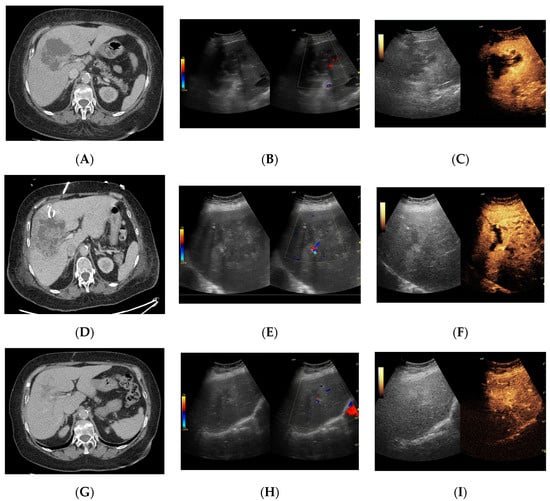

3.2.1. Arterial Phase

3.2.2. Early Venous Phase

3.2.3. Late Venous Phase